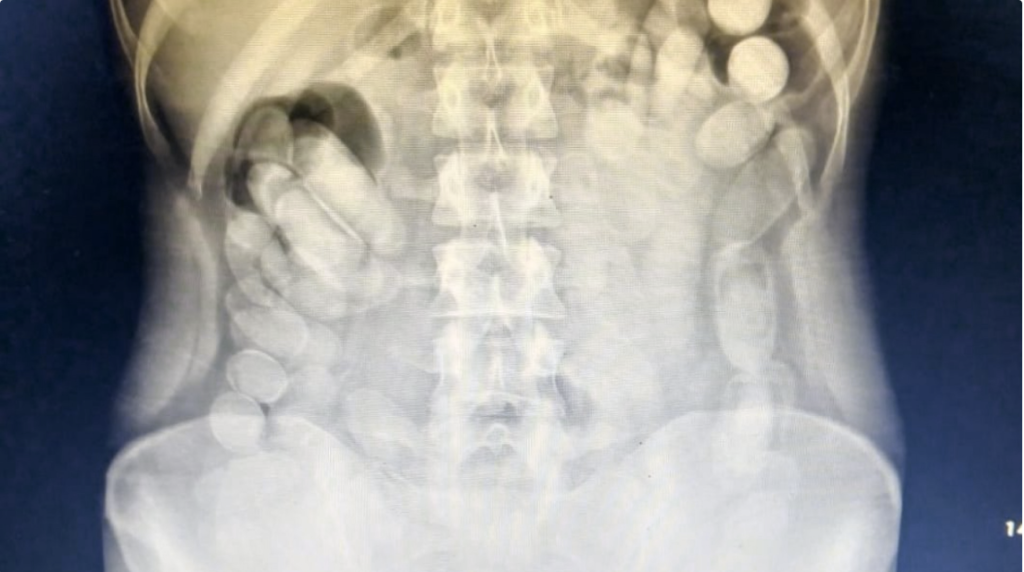

Una vez en el Nosocomio local, se le realizó una radiografía a la mujer mediante la cual se pudo observar la presencia de las dosis en su abdomen. Posteriormente, la involucrada evacuó 106 cápsulas.